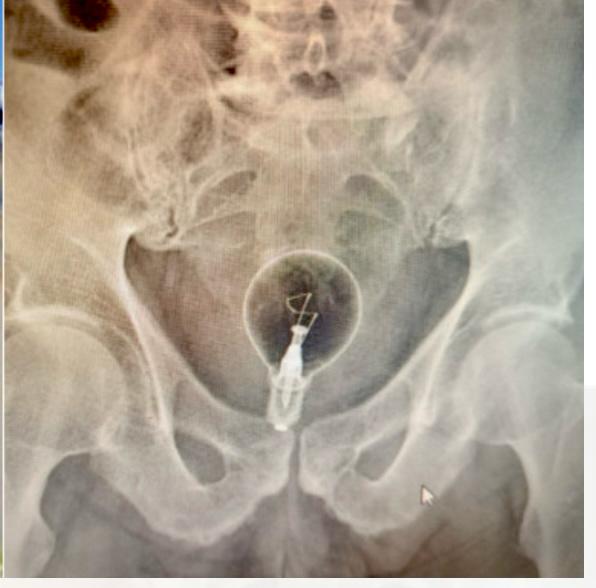

Lecce — Un episodio insolito e delicato ha visto protagonisti ieri mattina un uomo di 85 anni e il personale sanitario dell’ospedale “Fazzi” di Lecce. L’anziano, residente in un piccolo comune della provincia, ha chiesto aiuto al 118 dopo essersi trovato con una lampadina conficcata tra ano e retto.

Dopo gli esami diagnostici, l’uomo è stato trasferito al reparto di endoscopia per la rimozione dell’oggetto. Successivamente è stato ricoverato in chirurgia generale per monitorare il quadro clinico e garantire un completo recupero.